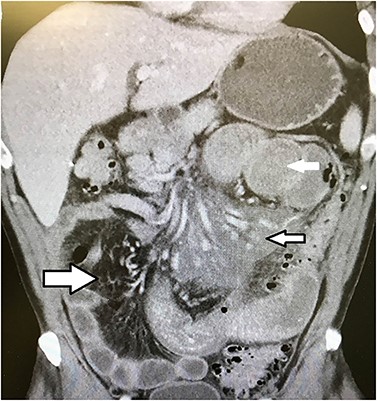

A large necrotic mesenteric lymph node with a ruptured capsule showing purulent drainage.

Emergent laparotomy was performed. He was found to have multiple enlarged necrotic mesenteric lymph nodes with purulent material draining from the capsule of the nodes (Fig. 2). Several large areas of the proximal mesenteric fat were necrotic with vascular occlusion and thrombosis, which was causing ischemia of the proximal jejunum. The proximal jejunum was very dusky and dilated, while the distal small bowel and colon was normal. The duodenum was spared. The necrotic fat and lymph nodes extended down to and around the superior mesenteric artery, where multiple side branches off the artery showed no blood flow by Doppler examination. The ischemic small bowel was excised along with its mesentery down to the superior mesenteric artery, to include the excision of the necrotic lymph nodes (Fig. 3). The bowel was left in discontinuity, and the patient was taken to the intensive care unit with a temporary abdominal closure. He was taken back to the operating theatre the next day for a second look, and the remaining small bowel was found to be viable and healthy. A duodenal to distal jejunal anastomosis was performed and the abdomen was closed.